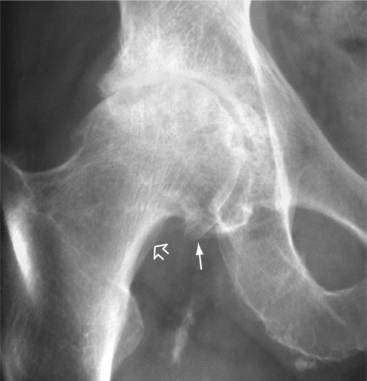

OA is diagnosed by correlation of history, physical examination, radiologic findings (Figs. 27-3 and 27-4), and laboratory tests, which rule out rheumatic disease. Box 27-6 lists radiographic changes associated with OA. The history of location of symptoms, symptom duration, functional limitations, trauma, medical comorbidities, and family history helps guide the physician in making the diagnosis.

Figure 27-4 Osteoarthritis of the hip. The anteroposterior view of the hip shows complete cartilage space loss superiorly. There is osteophytic lipping from the femoral head, especially medially (arrow), and buttressing bone (open arrow) is present along the femoral neck. (From Harris ED: Kelley’s textbook of rheumatology, ed 7, Philadelphia, 2005, Saunders.)